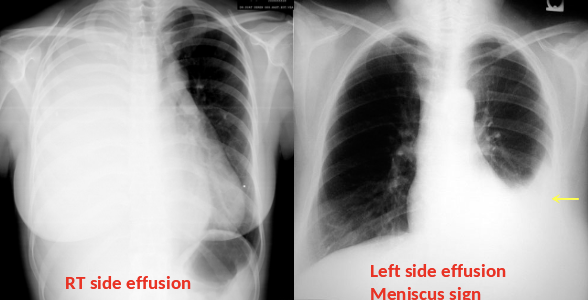

Supportive Findings:

- Typically unilateral blunting of the costophrenic angle Â

- Homogeneous density with a meniscus-shaped margin (meniscus sign)Â

- Large effusion â Complete opacification of the lung â Mediastinal shift â Tracheal_deviation away from the effusion (space-occupying lesion)